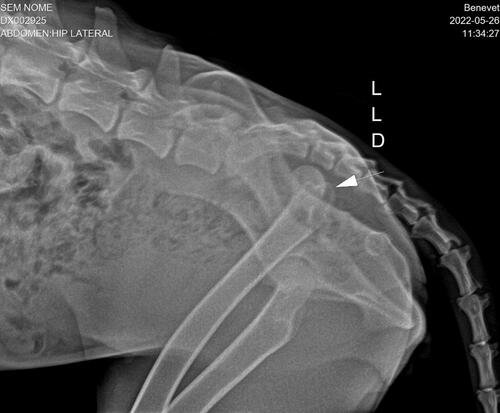

Serena é uma Pastora Belga de Malinois, que infelizmente é mais uma vítima de maus tratos, ela esta desnutrida, com alguns machucados, e além disso, ela também está com a perna luxada, houve um deslocamento da cabeça do fêmur, provavelmente em decorrência de uma batida muito forte! Foi feito um raio-x no hospital veterinário Benevet, e após o diagnostico veterinario, ela precisará fazer uma cirurgia, Sutura Iliofemoral, para colocar o femur no lugar, pois atualmente ela não esta conseguindo apoiar a perna direita no chão!